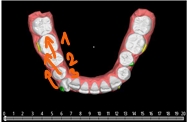

Wykonano ewaluację zaproponowanych sekwencji ruchów zębowych w dostarczonym planie 3D jednej z polskich firm nakładkowych. Opisano jak kształt i wielkość przemieszczanych zębów może wpłynąć na skuteczność kliniczną zaplanowanego leczenia.

Cyfrowy plan leczenia przeanalizowano pod kątem osiągnięcia klinicznego celu zaplanowanego przez lekarza. Zaproponowano modyfikację ruchów zębów wg ich zakresu oraz sekwencji.

- Zmienić typ ruchu d.13 (z derotacji wokół długiej osi na ruch wahadłowy)

- Zmniejszyć ruchy dowargowe d.12, d.11.

- Zmniejszyć ruch dowargowy d.42

- Zmienić sekwencję ruchów zębów d.43, 44, 45 (najpierw zdystalizować 45,44 by następnie derotować 43)

- Wziąć pod uwagę inną opcję na derotację d.35 ( w pierwotnej wersji brakuje należytej przestrzeni do tego ruchu).

- Przemyśleć podział sekwencji ruchów na etapowe (nie wszystkie zęby przemieszczać jednocześnie).